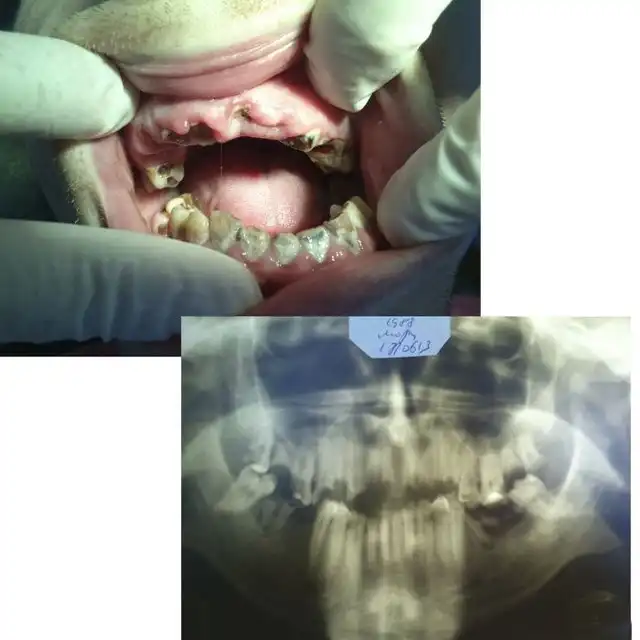

Угадайте, а сколько лет этому пациенту? По понятным причинам я не фотографировал его лицо полностью… Изначально он обращался около двух месяцев назад с переломом нижней челюсти в области суставного отростка слева, и шины наложить ему не могли, т.к. зубов целых почти нет… Был направлен в областную больницу, где походил с пращевидной бинтовой повязкой, и был отпущен домой… Остеосинтеза никто ему не делал. А потом спустя месяца два попал ко мне, после того как у себя на работе упал и ударился тем же местом)))) Очень «правдоподобно»… Но не в этом суть, парню 25 лет!!! Считает, что зубы разрушены, т.к. он на вредном производстве на заводе работает. Но гораздо более вероятная причина — нежелание чистить зубы. На фотографии видно, сколько там налета. И так многие выдумывают самые невероятные причины: работа с кислотой, жизнь в тайге, дальние плаванья, утрата зубов за один месяц после родов и т.п. Все это может повлиять в какой-то степени, но на деле у всех этих пациентов ужасная гигиена и последнее посещение стоматолога при царе Грохе. А у нашего парня зато татуха на всю правую руку, и на то, чтоб ее сделать, он нашел и время, и деньги, и желание… Это наш менталитет… Ездить на дорогой машине, понаделать татух, пирсинг, ходить в дорогих шмотках, но при этом с грязными ушами и нечищеными зубами. Редко кто на приеме попадается с таким уровнем гигиены, чтоб можно было стоматологическое вмешательство проводить. Да-да, есть индекс гигиены специальный, и если он выше определенной величины, то удалять нельзя. Но на деле удаляю, т.к. если строго подходить, то принять можно будет 2-3 человек за смену, остальных отправлять чистить зубы… Но потом люди приходят и с удивлением спрашивают, почему лунка после удаления болит? Никому даже в голову не приходит, что одной из вероятных причин может быть помойка во рту… Так что, друзья, идете к стоматологу — почистите зубы хорошенько ( да и вообще их чистить надо)), даже этой мелочью вы обеспечите себе хорошее отношение врача, потому что чистый рот — большая редкость и приятная неожиданность для стоматолога( к сожалению).

А это его панорамная рентгенограмма. То, что обвел красным, надо удалять. В 25 лет этому парню надо ставить съемные пластиночные протезы. Это такие, как вы видели у своих бабушек и дедушек в стаканах на тумбочке у кровати…

Вот один интересный товарищ. Не мой пациент, но просили посмотреть… Несколько месяцев назад получил травму, перелом челюсти, но врачам об этом не говорил, догадались сами, лечился в областной больнице, был выписан, все было хорошо вроде бы уже, но недавно обратился к нам с остеомиелитом, флегмоной щечной области, неконсолидировавшимся( несросшимся) переломом нижней челюсти слева. Чтоб дойти до такого состояния нужно терпеть с появления первых симптомов с месяц минимум… На фотке виден не корень зуба. Это секвестр — некротизированный, отторгающийся участок кости нижней челюсти. Мужик поедет к челюстно- лицевым хирургам…

Это секвестр, который я достал пинцетом, просто он уже практически свободно лежал в полости рта и не был связан с нижней челюстью, остальные секвестры будут удалять челюстно-лицевые хирурги в стационаре. Операция называется секвестрэктомия. В поликлинике такие операции делать нельзя.